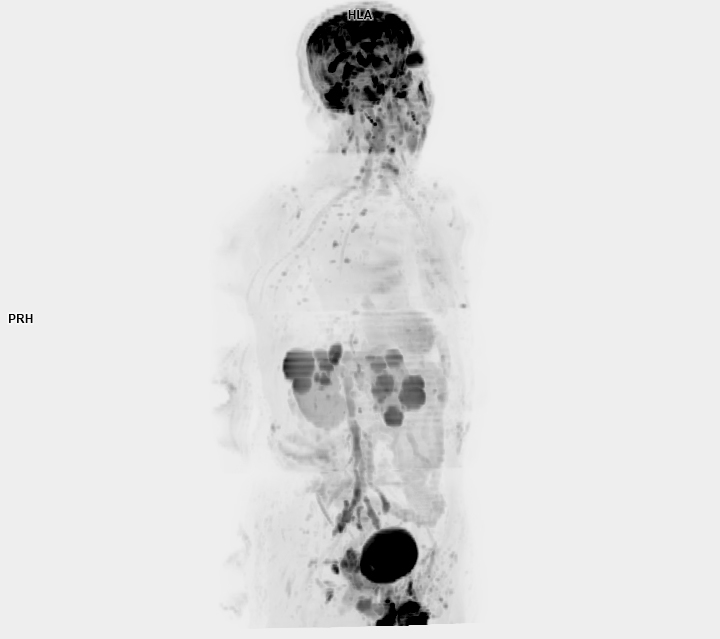

• 3 TESLA MR ÇEKİM GÖRÜNTÜLERİ

3 Tesla MR Çekim Görüntüleri

• 3 Tesla MR Çekim Görüntüleri